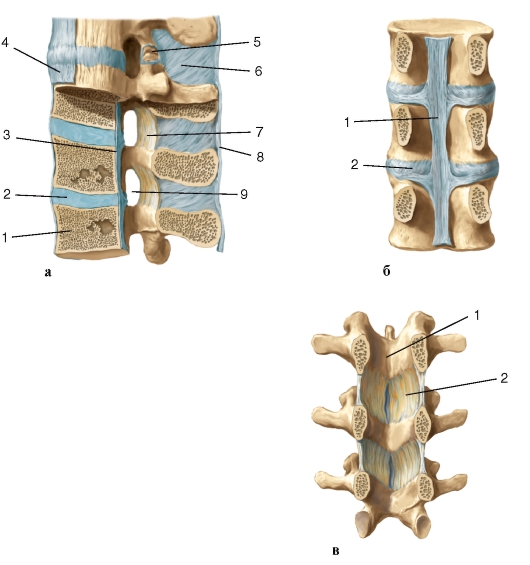

Структура и анатомия синдесмоза: научные иллюстрации